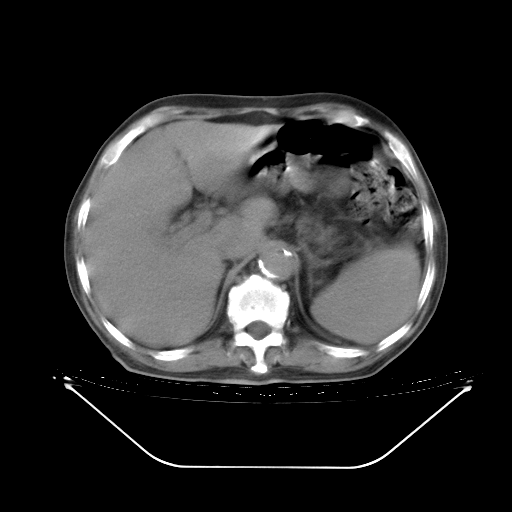

今天复查肺部CT,发现双肺广泛磨玻璃样改变。所以我把3月19日和5月9日相隔50天的肺部CT上传。请大家会诊。

5月9日肺部CT(在4月27日齐鲁医院肺部CT描述部分肺组织磨玻璃样改变,12天后肺组织广泛磨玻璃样改变)

大致读了系列胸部CT:纵隔窗无明显异常,肺窗:从4、27至今:主要是双肺中下野外带可见毛玻璃样改变,目前处于急性肺泡炎阶段,至于原因考虑1、结替组织或胶原血管性疾病所致?2、恶性疾病如恶组在肺部所致的表现或细支气管肺泡癌?3、药物或其它原因如肺蛋白沉着症所致肺泡炎目前不太可能?总之,明天就去请我院的呼吸科、感染科、血液科和临免专家会诊哈。